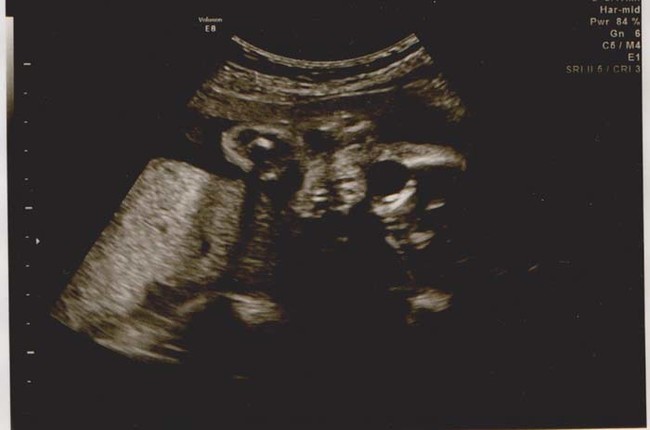

เดี๋ยวนี้ยามตั้งครรภ์คุณแม่เกือบทุกคนก็นิยมอุ้มท้องป่อง ๆ ไปให้คุณหมอทำอัลตราซาวด์ จะได้เช็กดูว่าเจ้าตัวน้อยข้างในอยู่สบายแข็งแรงดีหรือเปล่า แถมยังได้จะเห็นไปหน้าเค้าโครงใบหน้าลาง ๆ ของเจ้าหนูด้วย ดูแค่เงาก็เดาไปกันใหญ่แล้วว่าเหมือนใครมากกว่ากัน จนอดใจไม่ไหวอยากรีบคลอดออกมาให้เห็นหน้าลูกน้อยตัวจริงเร็ว ๆ แต่ถ้ามาเจอ 13 รูปอัลตราซาวด์สุดสยอง ที่เรานำมาฝากจากเว็บไซต์ boredomtherapy เหล่านี้เข้าไปหน่อยล่ะก็... บางทีคุณอาจไม่แน่ใจแล้วล่ะว่า นี่ใช่ลูกฉันจริงหรือเปล่า !!

ถึงจะรักเด็กแค่ไหน แต่ถ้าคุณขวัญอ่อนเราขอเตือนกว่าอย่าเลื่อนลงไปดูดีกว่านะ...